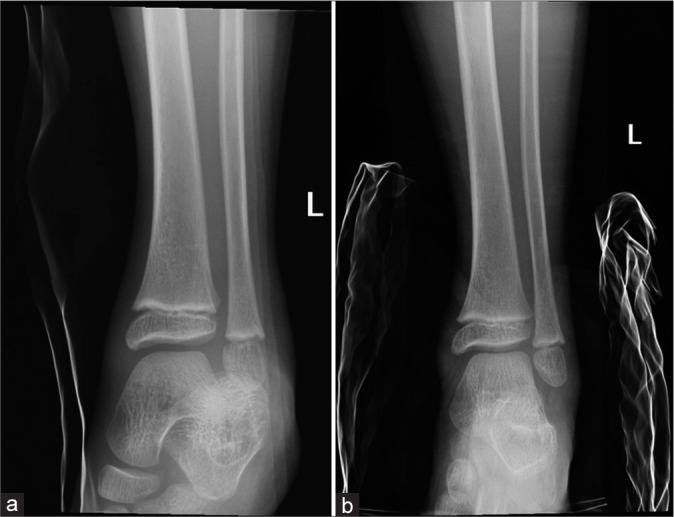

Objectives: The objectives of this study were to contribute to the limited existing knowledge about subtalar dislocations, analyze the computed tomography (CT) findings and advantages over radiography, and report the rate and potential risk factors of post-traumatic peri-talar osteoarthritis (OA).

Material and methods: A total of 23 cases of traumatic subtalar dislocation during a 15-year period at three regional hospitals were retrospectively reviewed.

Results: All 23 cases were closed dislocations. Successful close reduction was performed in 17 patients (73.9%) and 6 patients (26.1%) required open reduction and internal fixation. Twenty patients (87%) had associated foot and ankle fractures. Fractures of calcaneal medial tubercle were the most common (75%), followed by talar head (30%), sinus tarsi (25%), and medial malleolus (25%). The radiograph's sensitivity for identifying fractures was 48.1%. The mean follow-up period is 30 months. Symptomatic OA affected 8 patients (36.4%). No post-trauatic talar avascular necrosis was noted. Fractures were present in all of those patients with post-traumatic OA (100%). Three out of five patients who sustained high-energy mechanism injury developed radiographic OA (66.7%). Three out of six patients (50%) treated with open reduction and internal fixation also developed radiographic OA.

Conclusion: Subtalar dislocation remains a rare injury. It is strongly associated with foot and ankle fractures. Fractures of the calcaneal medial tubercle were the most common. The risk of post-traumatic symptomatic peritalar OA is high. CT is useful in detecting occult fractures and injured bony subregions. We postulated potential risk factors of post-traumatic OA (fracture, high-energy mechanism of injury, open reduction, and internal fixation); however, this requires further study.